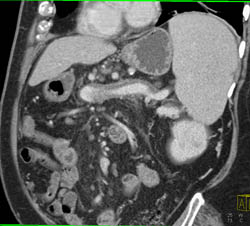

Partial Thrombosis of the Splenic Vein